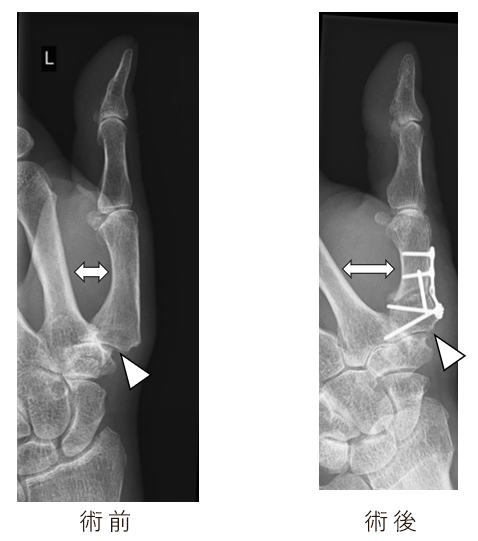

A.お薦めは中手骨楔状骨切り術です。30度の外転角度で骨切りをしてプレートで固定をします。

母指の外転が可能(⇔)となり、亜脱臼していたCM関節が整復され、関節裂隙(軟骨スペース)は修復されている(△)。

握力の低下がなく、症状の悪化の際にはさらにサルベージ治療が可能な術式です。手術時間は1時間30分程度です。